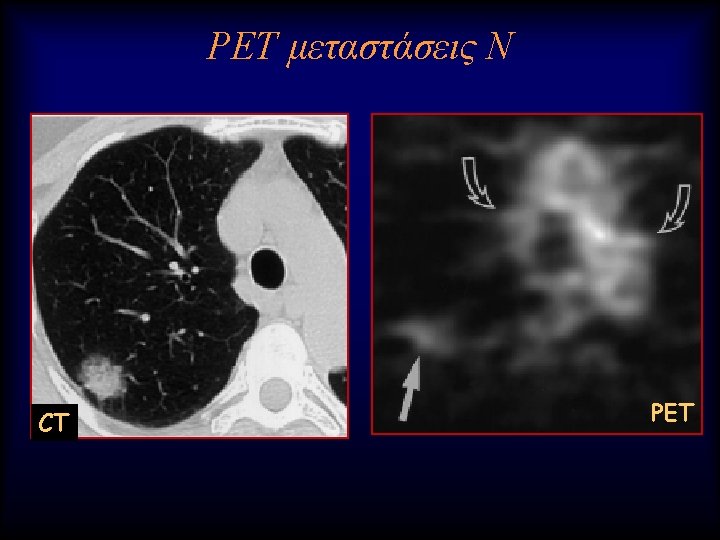

Lung nodule analysis • Evaluating Pulmonary Nodules Pulmonary nodules ≤ 4 mm have a low risk of being cancerous; nodules between 4 -8 mm are of intermediate risk for cancer; follow up CT scans for both categories are recommended on different schedules • Pulmonary nodules >8 mm and mixed solid/ground glass nodules are suspicious for cancer; percutaneous needle aspiration biopsy (PNAB), positron emission tomography (PET), or video assisted thoracic surgery (VATS) should be considered

FDG-PET/CT vs 3 T MRI